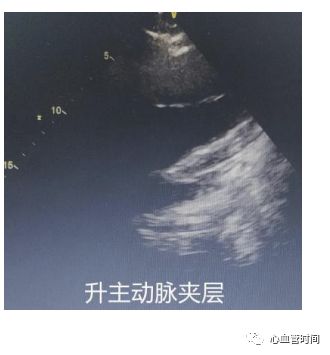

升主动脉升主动脉若明显增宽,且出现

片状回声时要考虑夹层可能,但需注意该切面往往出现

伪像较多,有个别患者超声可见明显飘动片状影,CTA 却未见异常。

升主动脉升主动脉若明显增宽,且出现

片状回声时要考虑夹层可能,但需注意该切面往往出现

伪像较多,有个别患者超声可见明显飘动片状影,CTA 却未见异常。